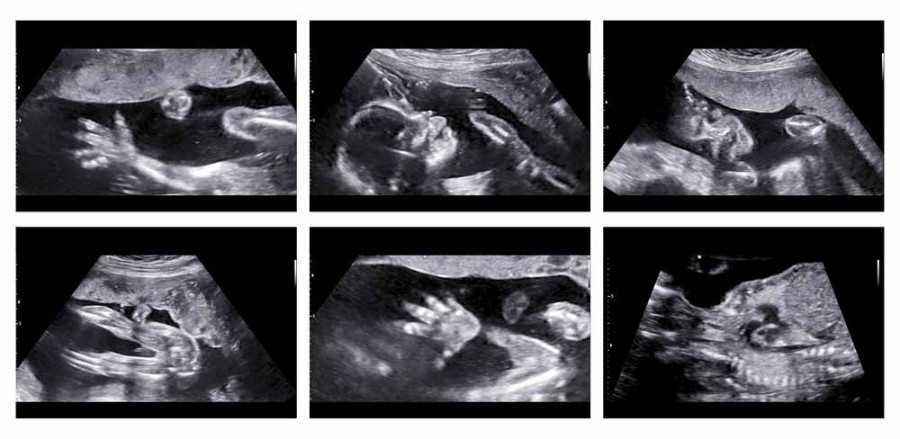

Janin sudah bisa tertawa dan menangis sejak dalam kandungan

Jika Ibu hanya tahu bahwa bayi menangis ketika pas dilahirkan, ternyata sang bayi sudah bisa menangis sejak dalam kandungan. Hal ini terjadi pada minggu ke-26. Penelitian yang dilakukan The Archives of Disease in Childhood membuktikan bahwa janin pada usia kehamilan minggu ke-26 terlihat menangis. Rekaman ini diperlihatkan melalui ultrasound dan menunjukkan bahwa janin menolehkan kepalanya, membuka mulutnya, dan berekspresi seperti orang menangis. Kemudian pada minggu ke-35 juga terlihat beberapa gerakan pada muka, menunjukkan seperti orang sedang tertawa.

Jadi kesimpulan pada penelitian ini bahwa sejak memasuki kehamilan minggu ke-26, bayi sudah mulai belajar untuk menggerakan otot-otot mukanya dengan cara melakukan ekspresi-ekspresi sederhana, seperti menangis dan tertawa.